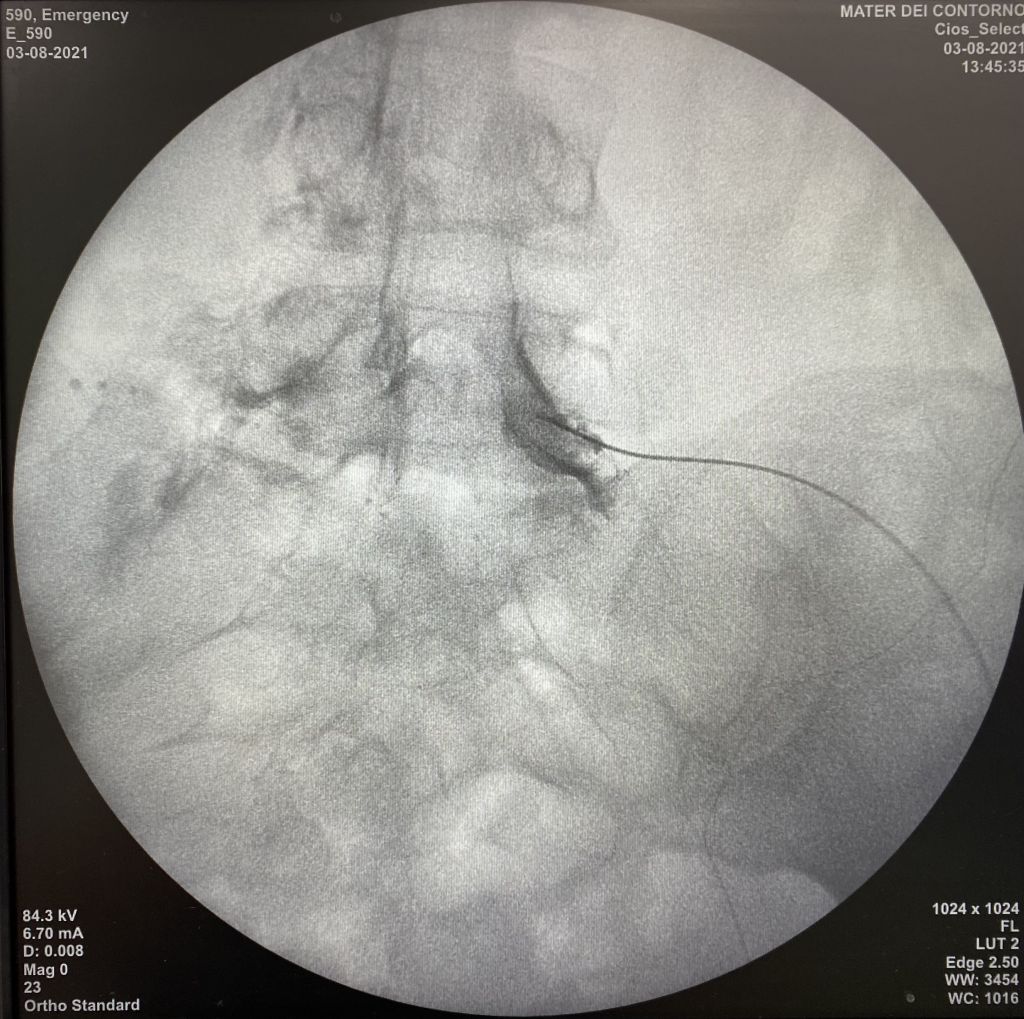

A infiltração da coluna, também chamada de bloqueio da coluna, denervação facetária ou bloqueio foraminal é um procedimento realizado pelo especialista em coluna que permite tratar a dor da hérnia de disco e outros problemas na região sem a necessidade de realização de cirurgia aberta. Ortopedista de coluna, especialista em coluna, infiltração da coluna

Geralmente, o procedimento dura menos de 1 hora e o paciente pode ter alta poucas horas depois. Não é necessária anestesia geral, apenas sedação leve para conforto e anestesia local. Na maioria das vezes, a melhora é imediata e pode persistir por vários meses. especialista em coluna,